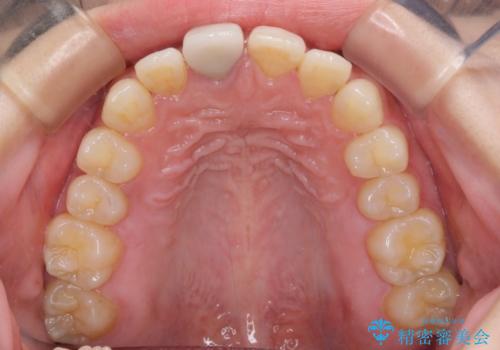

- 近医にて被せた前歯のクラウンの色の違いを気にして来院された患者様です。

オーダーメイドのオールセラミッククラウンにて補綴することとしました。

元々すきっ歯であったため、隙間を全て埋めると左右で大きさがアンバランスとなることが懸念されました。

違和感のない程度に隙間を小さくして、自然な見た目に仕上げました。